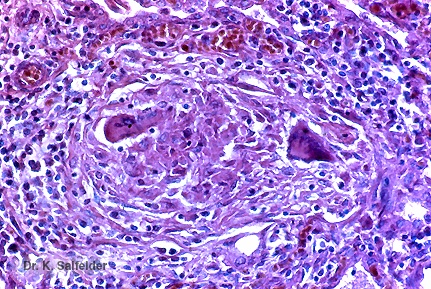

Abb. 17,13: Pneumozystose

Eine granulomatoese Entzuendung mit Riesenzellen kommt auch gelegentlich vor, ist aber selten bei dieser Infektion. HE-Faerbung